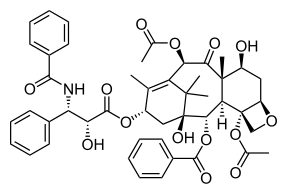

The nomenclature for paclitaxel is structured on a tetracyclic 17-atom skeleton. There are a total of 11 stereocenters. The active stereoisomer is (−)-paclitaxel (shown here).